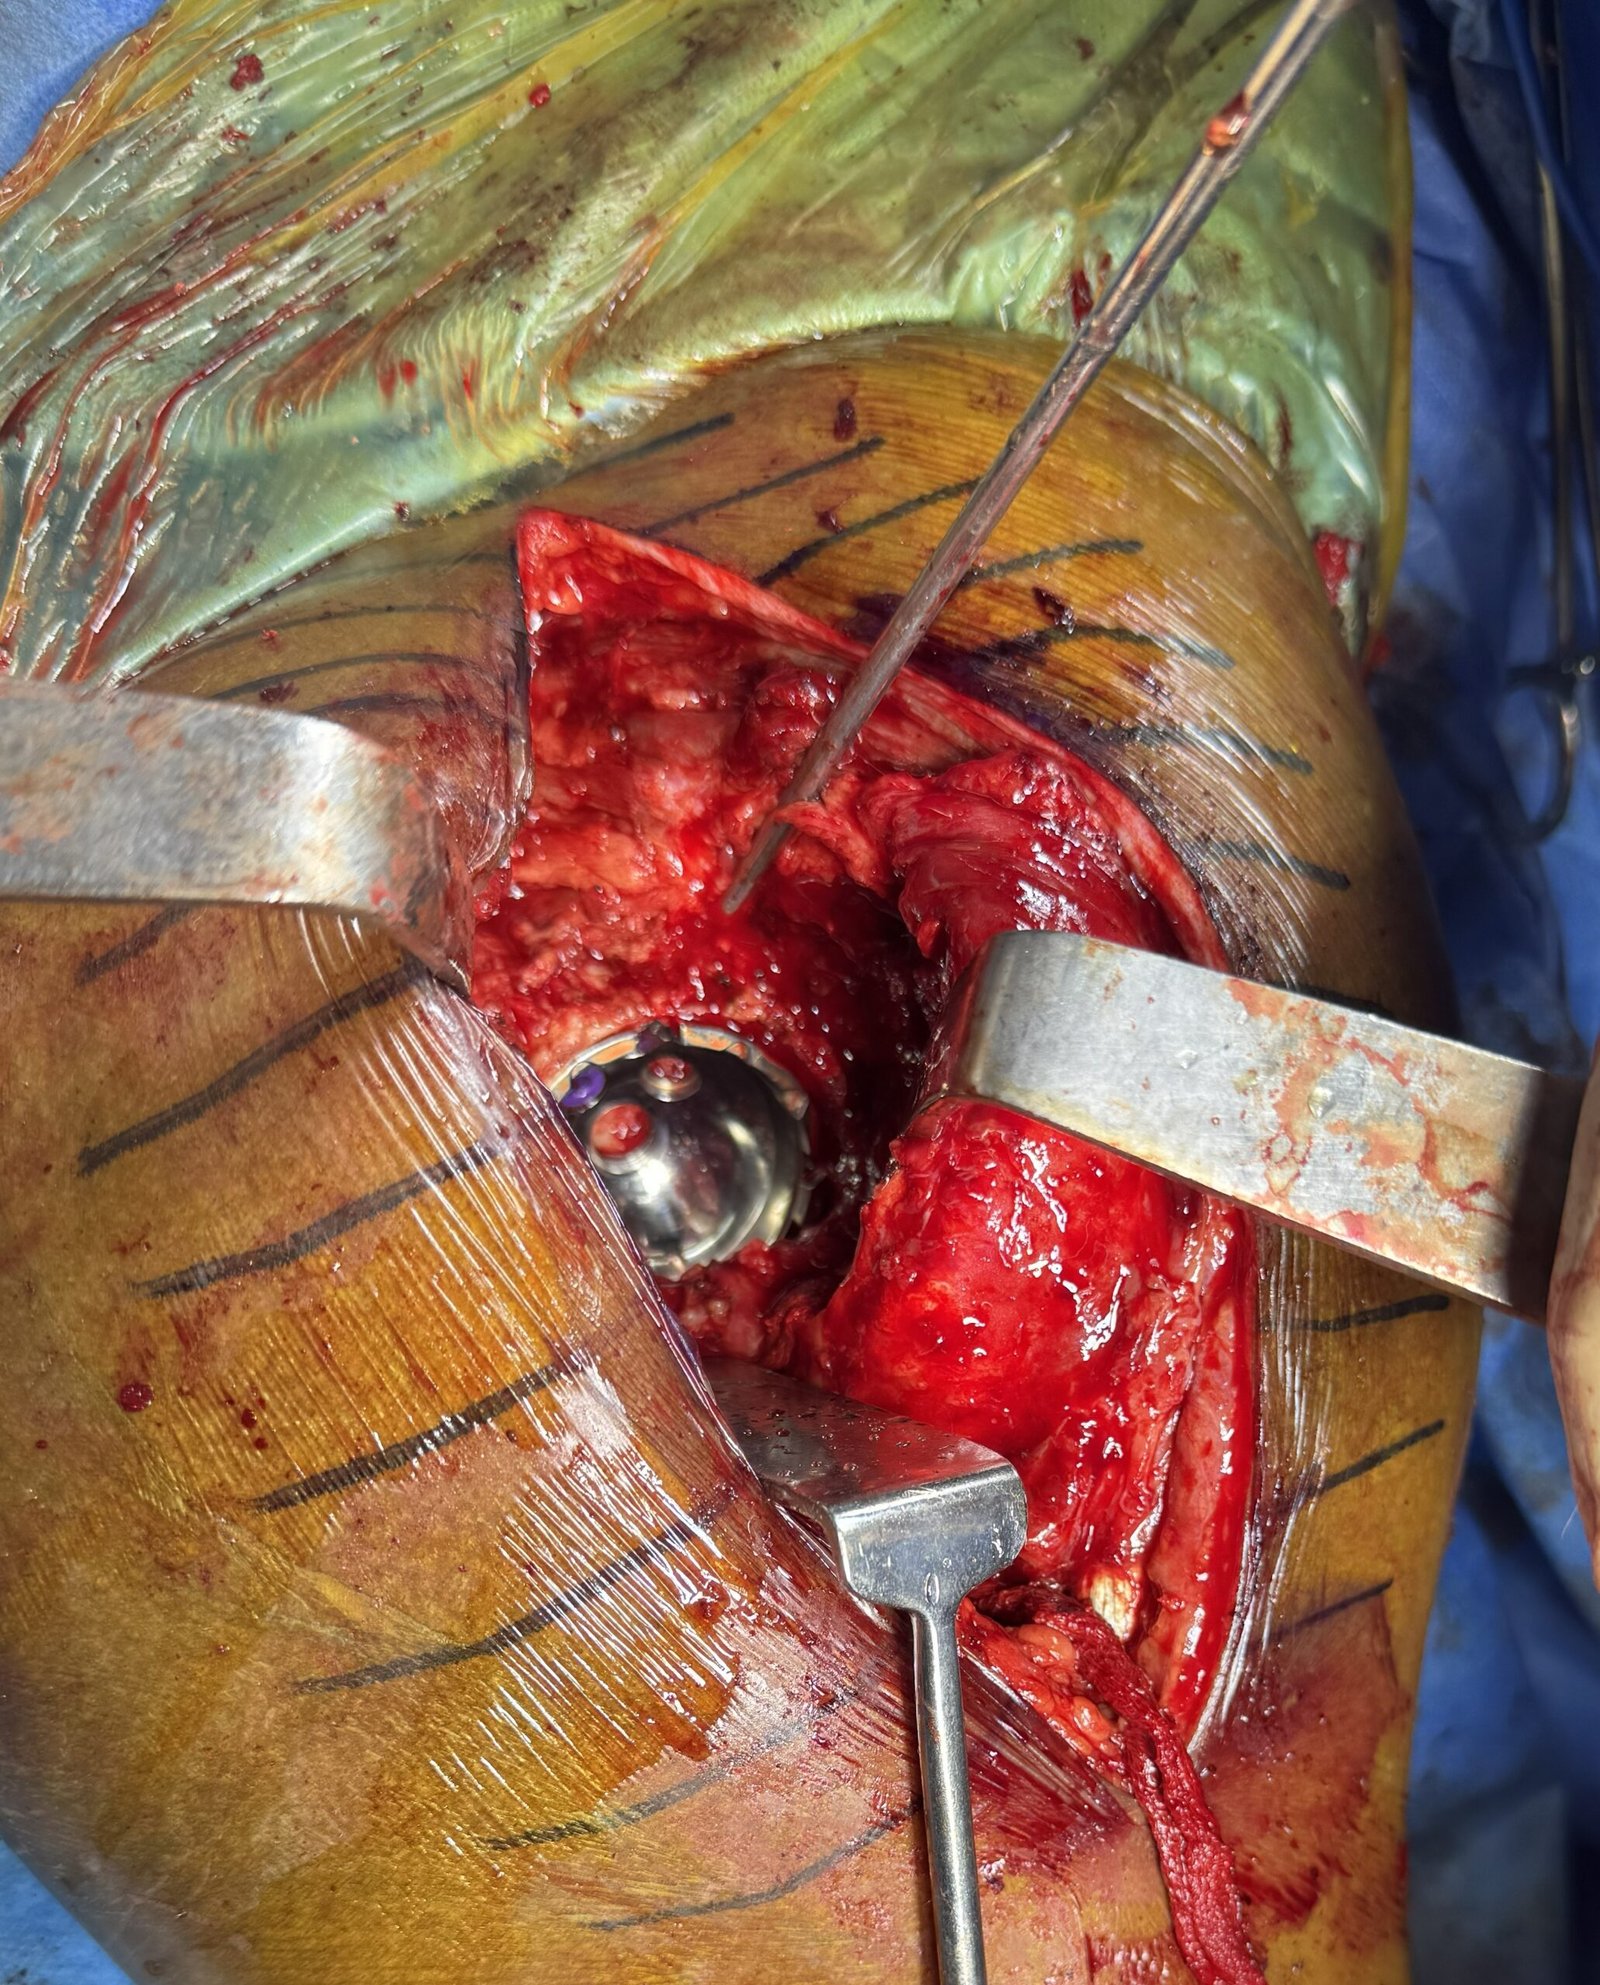

Cup Placement with screws

Thumbnail